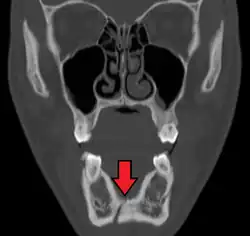

-

Panoramic radiograph of a simple mandible fracture of the right mandibular body, minimally displaced. Note that the teeth to the left of the fracture do not touch -